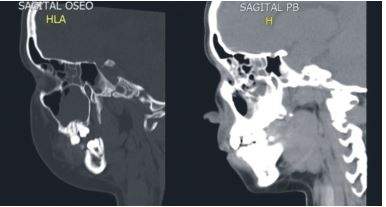

La tomografía axial (TAC) máxilo facial muestra velamiento de todas las cavidades perinasales con niveles hidro-aéreos de senos maxilares y senos esfenoidal (Figuras 2, 3 y 4), confirmando el diagnóstico imagenológico de PA.

Cuando el origen de la PA es dental, es necesario el control de la evolución del caso, mediante radiografías periapicales y TAC12; en este caso fue imprescindible la información dada por las imágenes del TAC para observar el velamiento de las cavidades de la región Máxilo facial y su adecuado diagnóstico.